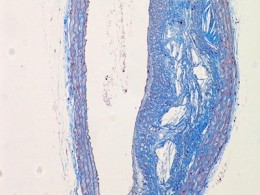

动脉粥样硬化...